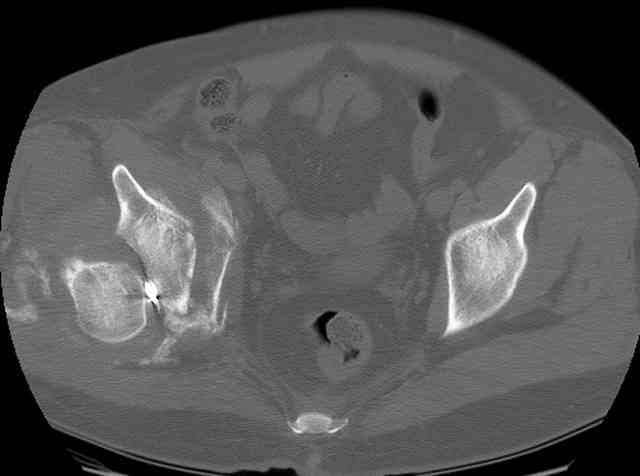

The 2nd example is of a motorcyclist with a transverse fracture-dislocation...he had a closed attempted reduction and placed in traction but the manipulative reduction was not concentric (not unusual for this injury pattern)...so the traction was adjusted to be just enough to disengage the head from the fracture (12#) until he could be cleared for surgery one day after injury...he was treated "urgently" then with a prone KL, clean the fracture, reduce and clamp it, screw it, support with a balanced plate, close, and enjoy...2-3hours, 400cc EBL, blah, blah, blah..